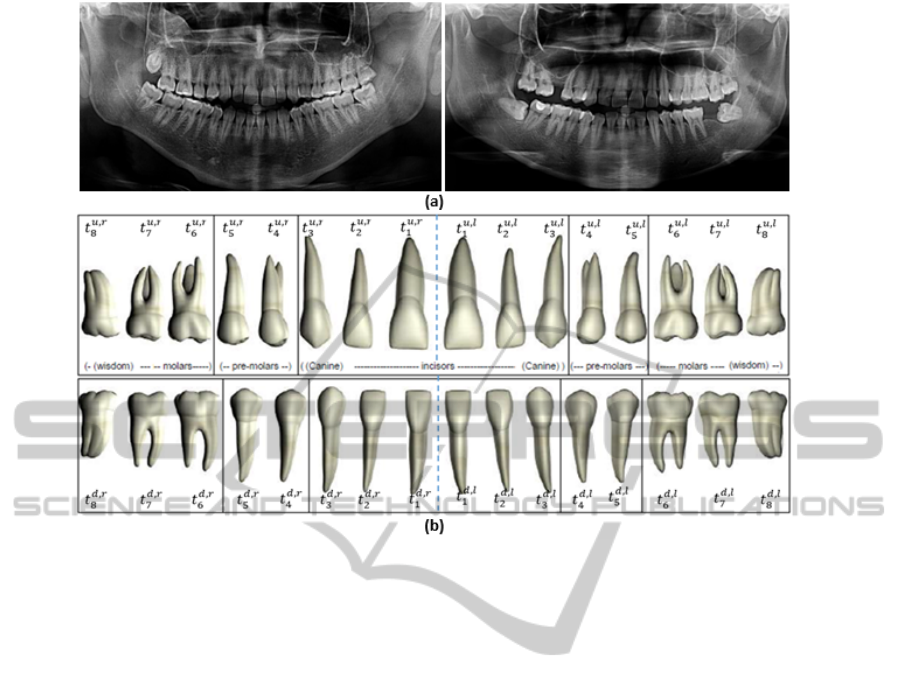

surance. Using dental panoramic radiographs (See

Figure 1(a)) for decedent identification satisfies the

limitations of the other biometrics, such as DNA and

fingerprint, due to the durable structure of teeth (Sen,